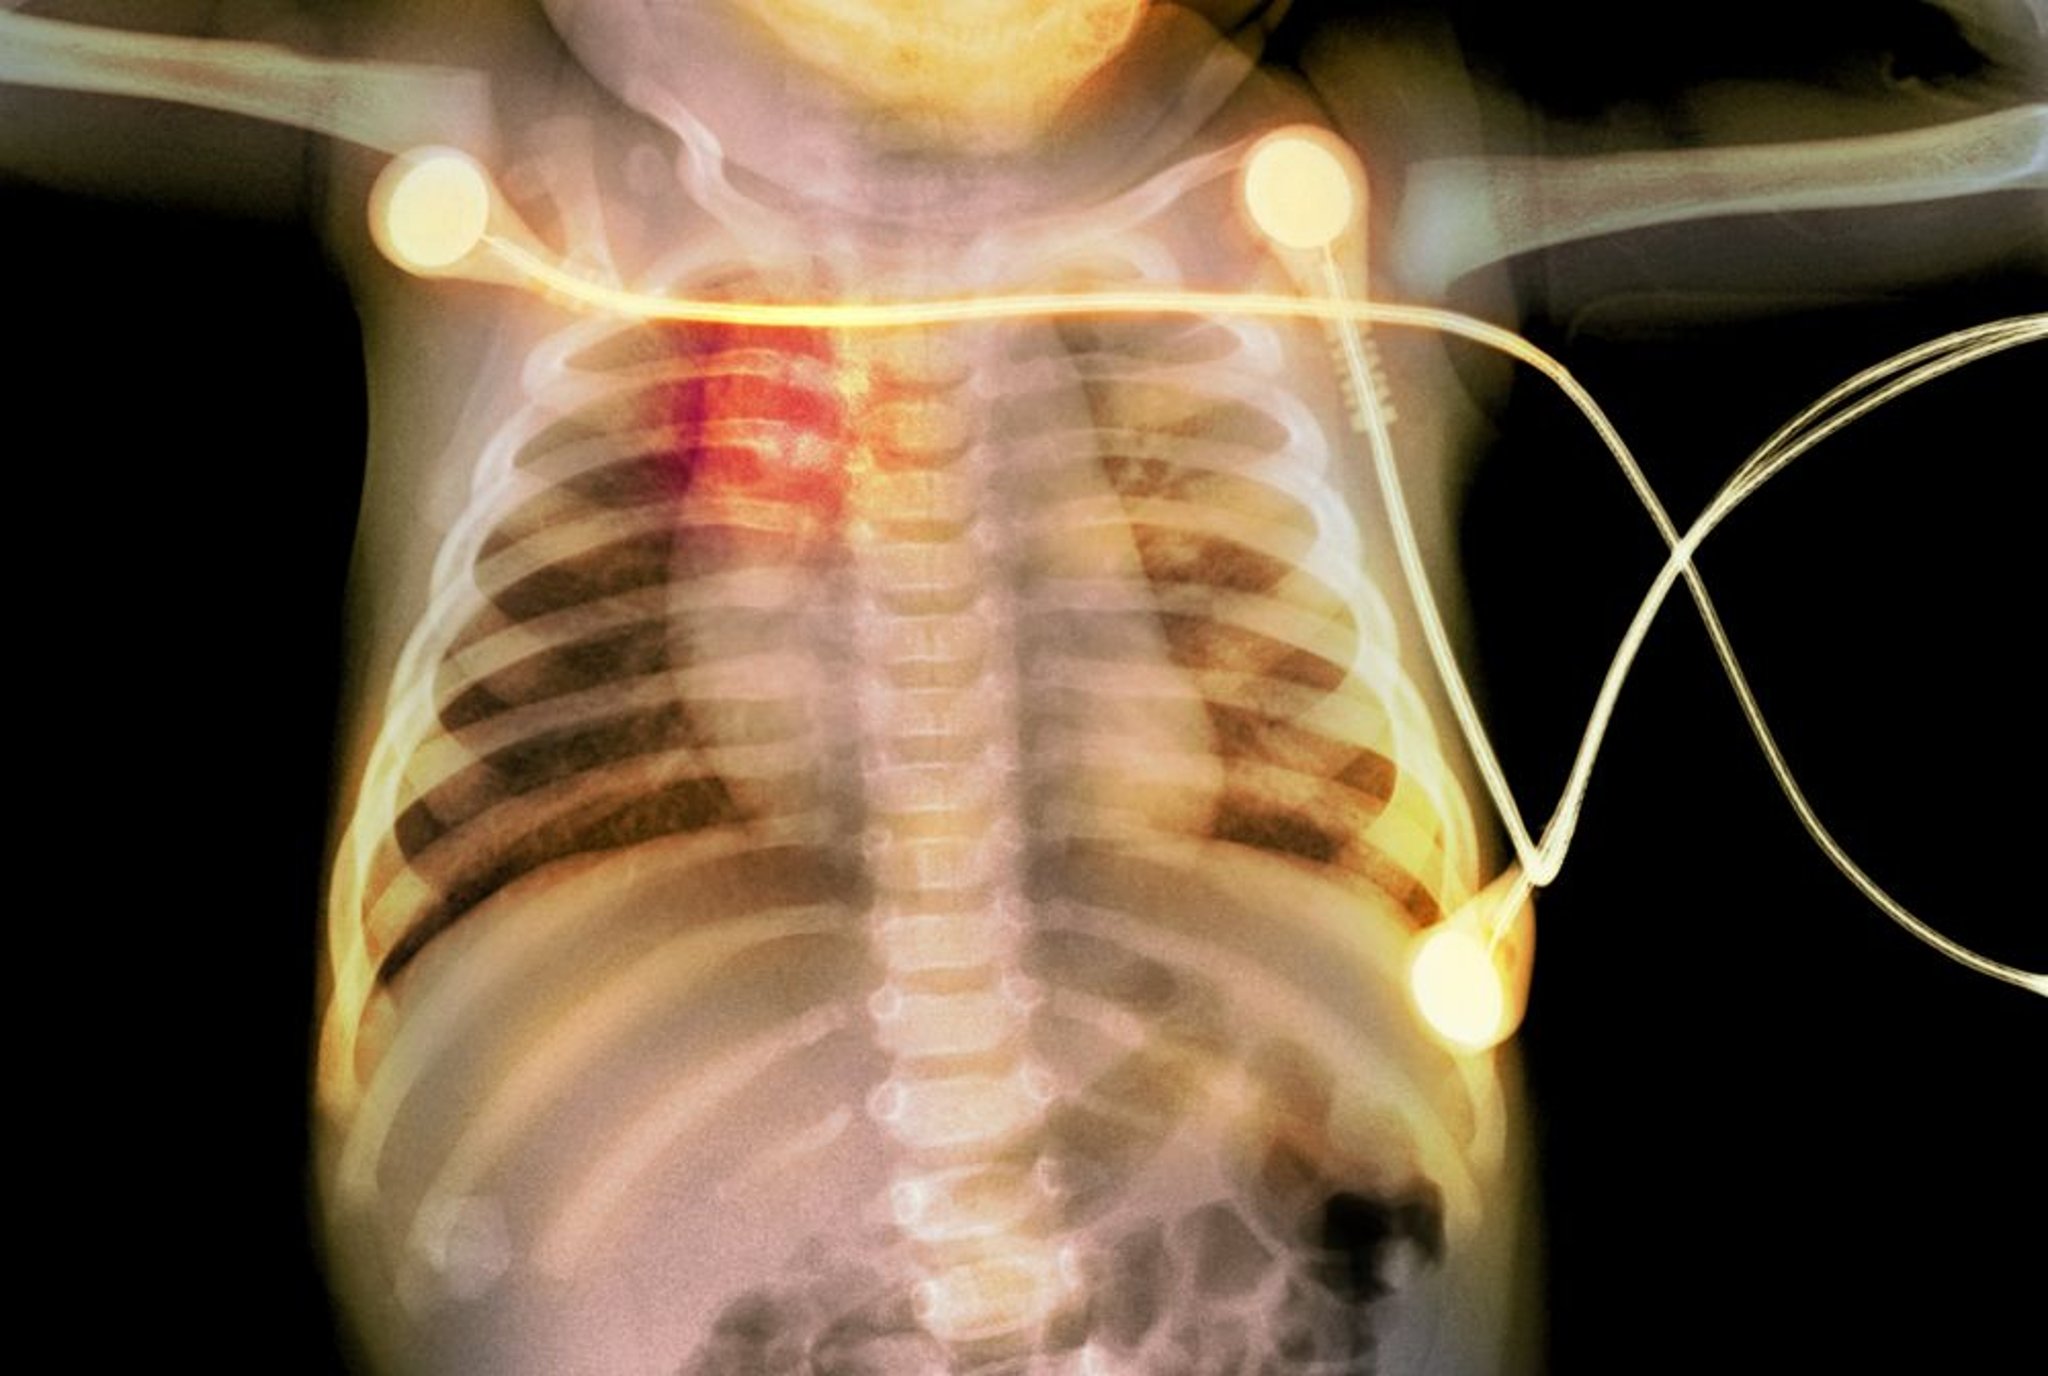

Переломы ребер у новорожденного

На рентгеновском снимке показаны переломы ребер (выделено красным) у новорожденного, что указывает на жестокое обращение с малышом.

PHOTOSTOCK-ISRAEL/SCIENCE PHOTO LIBRARY